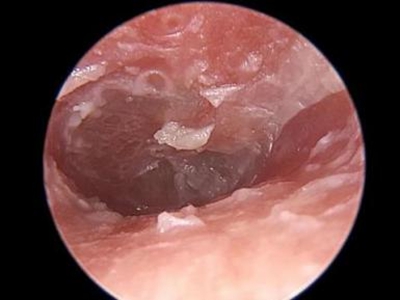

霉菌性外耳道炎外耳道结黑痂脱屑图

霉菌性外耳道炎患者外耳道周围有数量众多的黑白色鳞屑,稍微向上翘起,针尖至米粒大小,鱼鳞状排列,基地面呈紫黑色,并逐渐向外耳道深处侵袭。